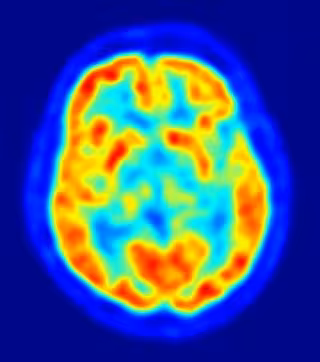

En la investigación anterior, Prinsloo identificó la ubicación de la actividad cerebral que contribuye a los aspectos físicos y emocionales del dolor crónico. Al dirigirse a las áreas del cerebro que están activas durante los episodios de dolor, 'neurofeedback' enseña a los participantes a entender las señales de dolor de manera diferente.

Los investigadores desarrollaron protocolos de entrenamiento que permiten a los pacientes volver a capacitar su propia actividad cerebral a través de 'neurofeedback' de electroencefalograma (EEG). La interfaz de EEG rastrea y registra los patrones de ondas cerebrales uniendo pequeños discos metálicos con alambres finos al cuero cabelludo. Las señales de ondas cerebrales se envían a un ordenador y se muestran a los participantes, quienes reciben recompensas visuales y auditivas cuando realizan ajustes específicos a los patrones de ondas cerebrales.

Los pacientes con CIPN también exhibieron firmas EEG específicas y predecibles en las regiones cerebrales específicas que cambiaron con 'neurofeedback'. "Observamos reducciones clínicas y estadísticamente significativas en neuropatía periférica siguiendo técnicas de neurofeedback --resume Prinsloo--. Esta investigación sugiere que 'neurofeedback' puede ser un enfoque valioso para reducir los síntomas de neuropatía y su impacto en las actividades diarias".